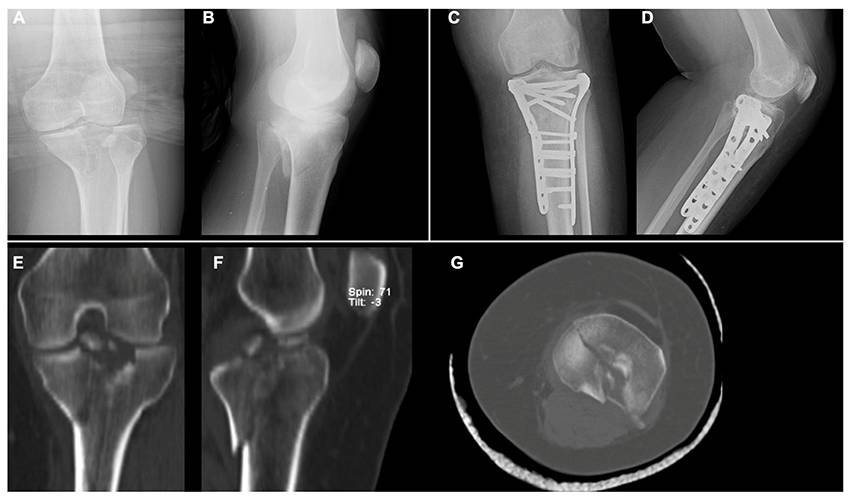

Predictors of reduction loss in tibial plateau fracture surgery: Focusing on posterior coronal fractures